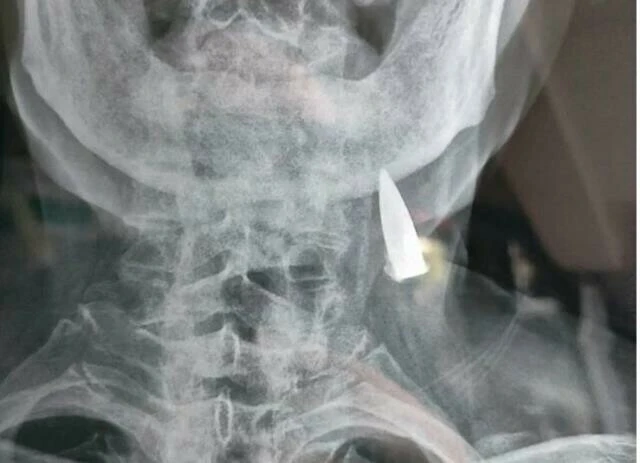

Zhao He'nin röntgenini gören doktor, meslektaşlarına da haber verdi ve doktorlar He'nin boynunda gördükleri manzarayla şoke oldular. He'nin boynuna saplı bir kurşun öylece duruyordu. Doktorlar, bu durumu He'ye söyleyince ise daha da ilginç bir bilgi edindiler. He, bu kurşunun tam 70 yıldan beri boynunda olduğunu söyledi ve İkinci Dünya Savaşı sırasında yaralanmasını anlattı.

Konuyla ilgili açıklamada bulunan Zhao'nun damadı, kayınbabasının savaş sırasında birçok kurşun aldığını ancak bundan habersiz olduğunu söyledi. Zhao ise yaşının ilerlemesi nedeniyle riskli olarak görülen ameliyatı kabul etmedi ve merminin çıkarılmasını istemedi. Yaşlı adam, bu mermiyle ölmek istediğini dile getirdi.